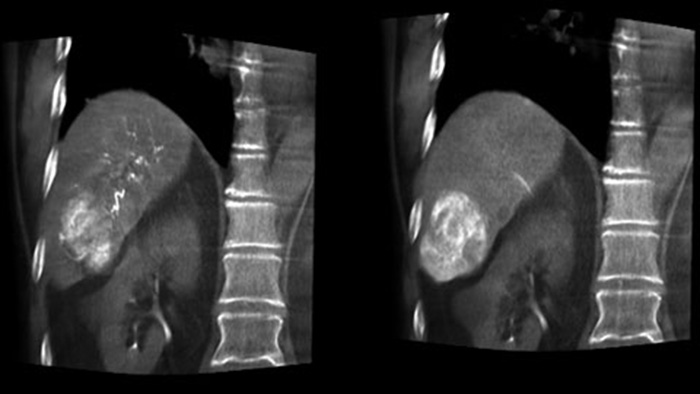

O CBCT Dual permite a aquisição 3D de uma fase arterial para visualizar estruturas vasculares e uma fase pós-arterial (fase retardada) para visualizar a acumulação de meio de contraste numa única etapa automática.5

A vista dupla permite a visualização simultânea de dois conjuntos de dados CBCT. Tanto a fase arterial como a fase retardada podem ser apresentadas ao lado uma da outra ou numa única vista de sobreposição fundida.